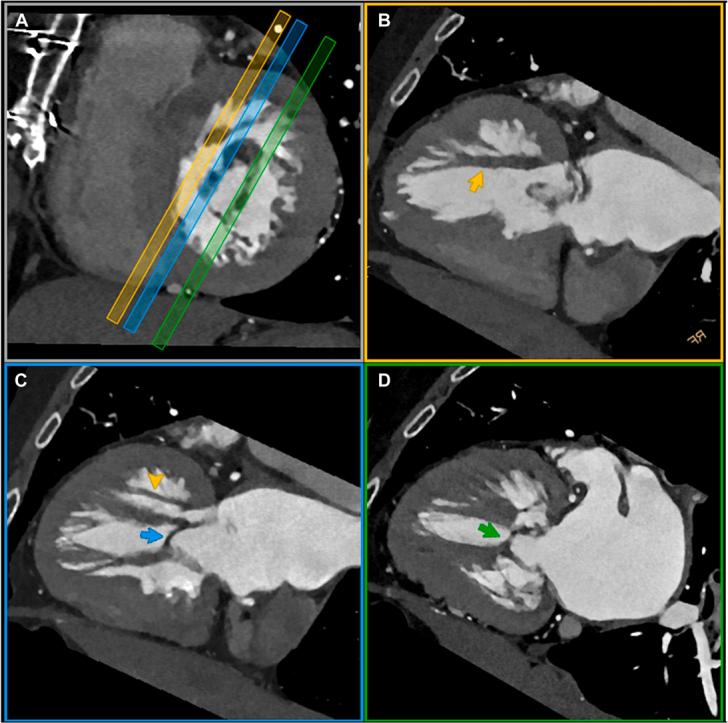

The Complex Hemodynamic Interplay between Mitral Arcade, Midventricular Obstruction, and Prosthetic Aortic Valve.

• MA is a malformation of valve tensor apparatus leading to early heart failure. • MA can be associated with subvalvar aortic stenosis, bicuspid AV, or aortic coarctation. • Multimodal imaging is invaluable in assessing mitral arcade.